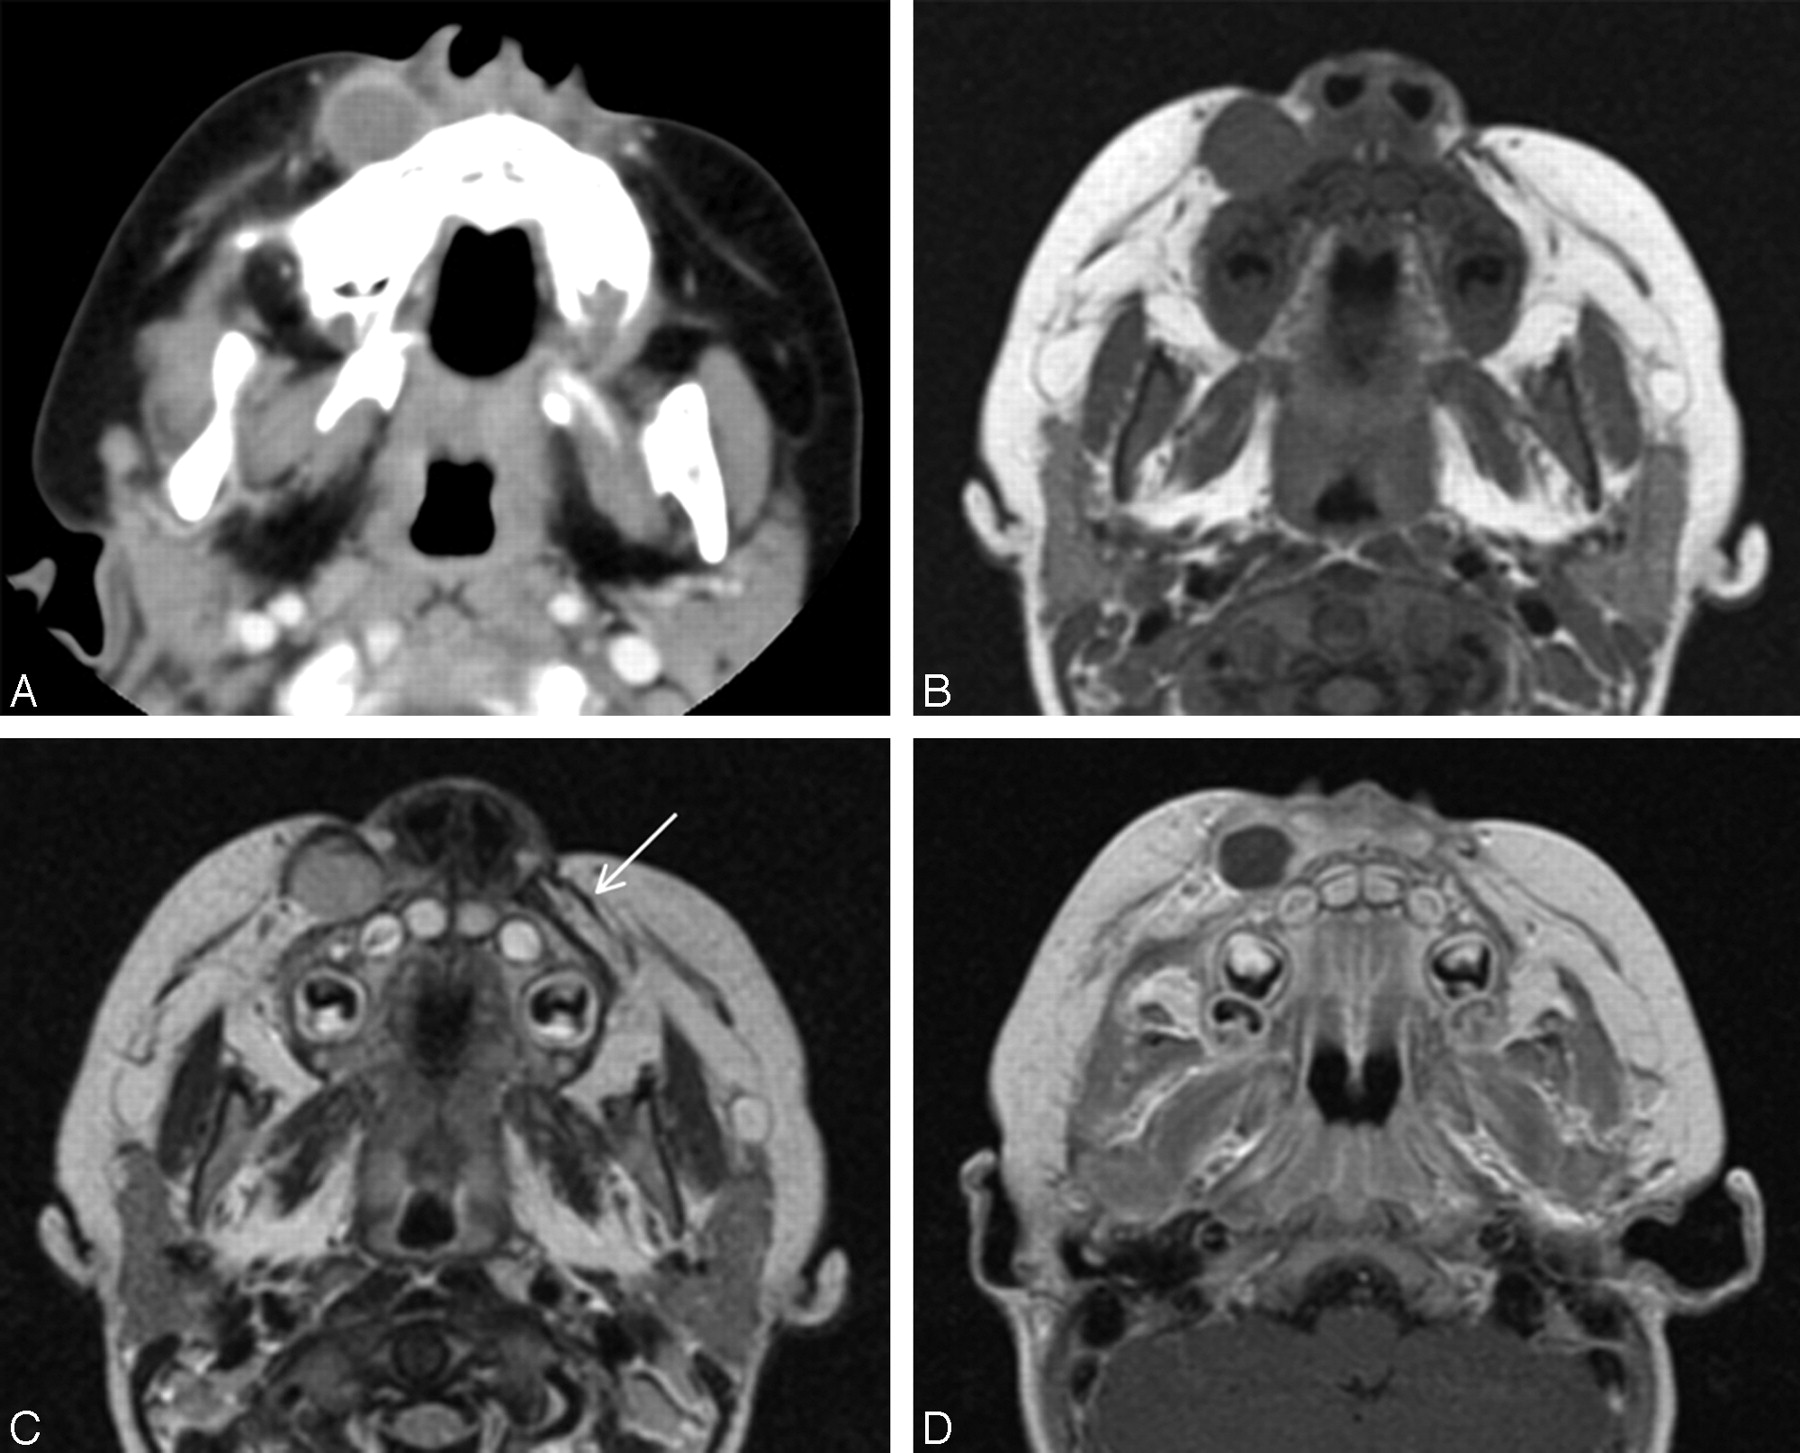

Case 5. Nodular fasciitis in the left supraclavicular fossa in an 11-year-old girl.

Contrast-enhanced axial CT scan (A) and coronal T1-weighted (B), T2-weighted (C), and contrast-enhanced fat-suppressed T1-weighted (D) MR images show a markedly enhancing, well-defined, ovoid soft tissue mass in the subcutaneous fat of the left supraclavicular fossa. The lesion has a partly serrated border on contrast-enhanced MR image (D). Compared with the adjacent muscle, the mass is isointense and significantly hyperintense on T1- (B) and T2-weighted (C) images, respectively.